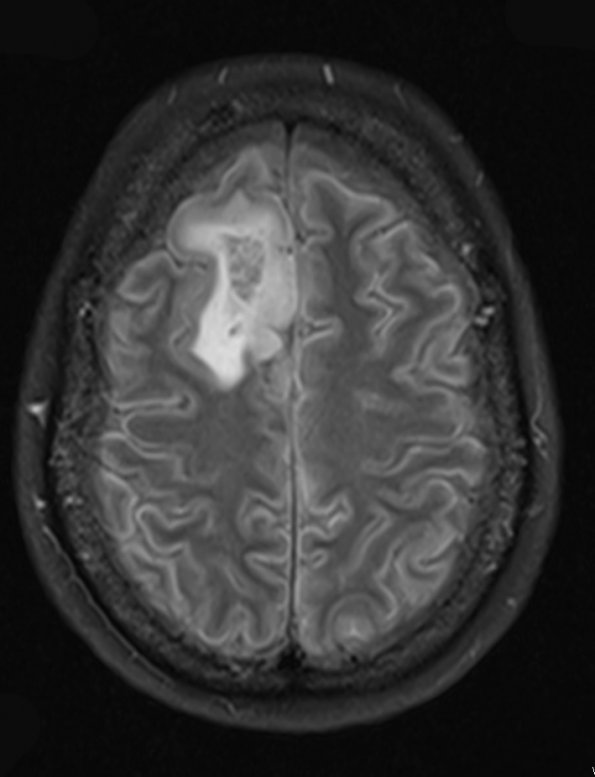

Case 4 History ---- The patient is a 42 year old woman who presented with a seizure. Operative procedure: Right frontal craniotomy for resection of tumor. 4A1-3 On MRI, a right frontal mass was noted. ---- 4A1 The tumor is hyperintense on FLAIR scan.